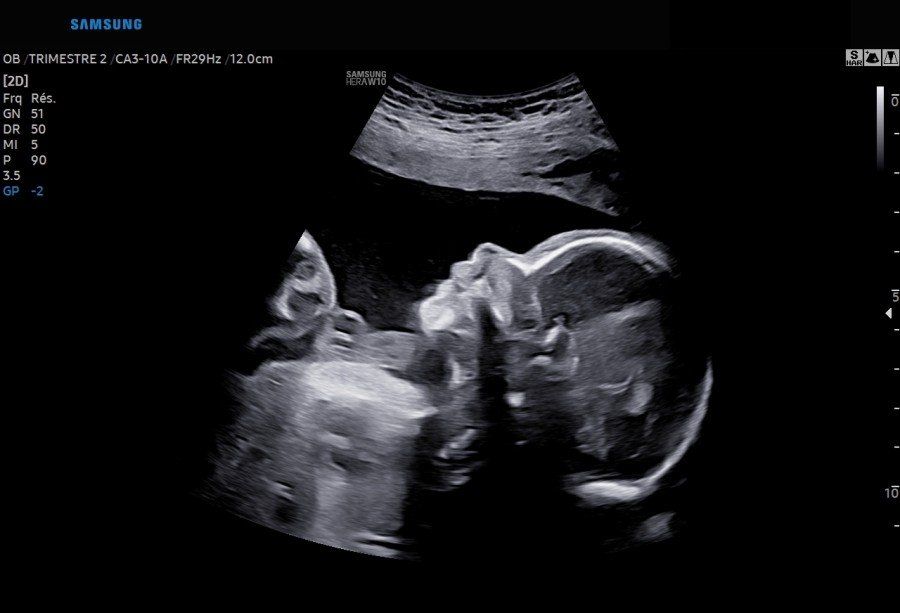

L’échographie obstétricale

L’échographie permet l’étude de votre bébé et de ses annexes (Placenta et cordon ombilical) durant votre grossesse.

Au cours de votre grossesse, trois échographies vous seront proposées systématiquement : au premier, second et troisième trimestre. D’autres examens pourront être réalisés en cas de nécessité et à la demande de votre médecin, gynécologue ou généraliste, ou de votre sage-femme.

Entre la 21° et 23° semaine d’aménorrhée

Cette échographie vous sera proposée de façon systématique par votre médecin.

Son objectif est de :

- S’assurer de la bonne vitalité de votre bébé par la présence de mouvements actifs et de l’activité cardiaque.

- S’assurer de la bonne croissance de votre bébé en mesurant différentes parties du corps (tête, abdomen, membres).

- Réaliser une étude morphologique c’est à dire la recherche d’images inhabituelles pouvant orienter vers des anomalies.

Si vous le souhaitez et si la position du bébé le permet, votre médecin pourra vous dire le sexe de votre enfant.

- Étude du Placenta, du cordon ombilical et du liquide amniotique.